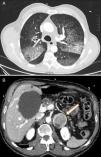

A 68-year-old male was seen in the emergency room after an episode of frank hemoptysis associated with oppressive chest pain, nausea, sweating and pallor. Dyspnea, cold sweats and pallor were confirmed on physical examination. BP>180/100mmHg, HR 120bpm. There were no significant changes on ECG and bilateral diffuse alveolar pattern was observed on chest X-ray. Laboratory test parameters of note included blood glucose 257mg/dl, leukocytosis with neutrophilia, hemoglobin 14g/dl (MCV normal), creatinine 1.19mg/dl, urea 62mg/dl, troponin T 596.6ng/l and CK 186U/l. Arterial blood gases were compatible with hypoxemic respiratory failure (PaO2 51.4mmHg). Non-ST segment elevation acute coronary syndrome with hemoptysis was suspected, so the patient was admitted to the ICU where double antiplatelet therapy was initiated but not anticoagulation, due to hemoptysis. The patient had another episode of frank hemoptysis associated with a hypertensive crisis requiring oxygen therapy and intravenous bolus administration of methylprednisolone. The clinical picture improved within hours with normalization of renal function and anemia (Hb 10.9g/dl). When the patient was interviewed again, he reported episodes of headache, sweating and palpitations on performing Valsalva manoeuvers. CT showed a crazy-paving lung pattern, ground-glass consolidations and interlobular septal thickening, compatible with alveolar hemorrhage (Fig. 1A) and heterogeneous left adrenal lesion 46mm×40mm (Fig. 1B). Raised catecholamine and metanephrine levels in urine (noradrenaline 1208.4μg/24h, adrenaline 532μg/24h, normetanephrine 5748.6μg/24h, metanephrine 12,281.6μg/24h) confirmed the diagnosis of pheochromocytoma. The patient was treated with alpha blockers (phenoxybenzamine 10mg/8h), later combined with a beta blocker (propranolol 10mg/8h). After 7 days of progressive improvement, fiberoptic laryngoscopy revealed pharynx and larynx free of bleeding and bronchoscopy was normal. Bronchoalveolar lavage contained no malignant cells and abundant hemosiderophages (>20%). Anti-DNA, c-ANCA, anti-MPO and anti-GBM antibodies and cultures were negative. After the patient stabilized, left adrenalectomy was performed by laparoscopy; the pathology examination revealed pheochromocytoma with malignant histological features. During follow-up the patient remained asymptomatic and all tests requested were normal (2 months after the episode, the patient had a PaO2 of 85mmHg).